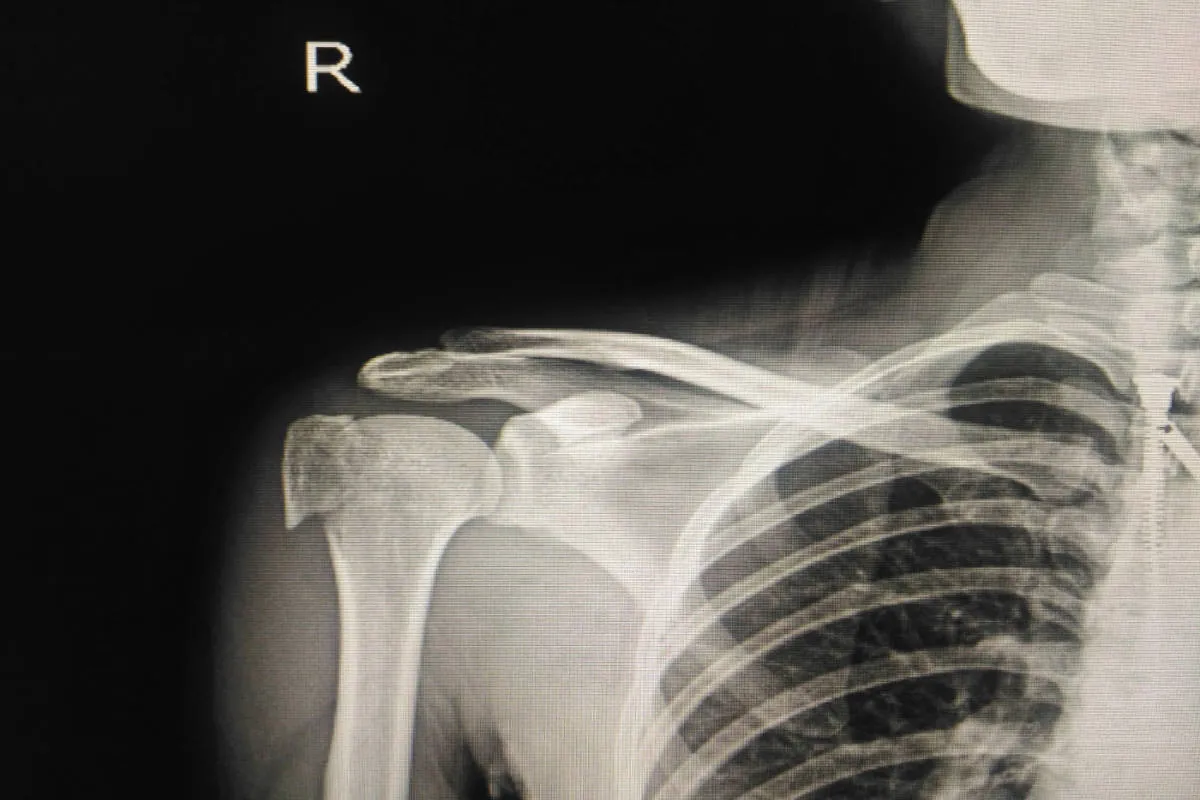

- Diagnoza opiera się na RTG, a w skomplikowanych przypadkach na TK.

Złamanie nasady bliższej kości ramiennej to uraz, który dotyczy górnej części kości tworzącej ramię, tej znajdującej się najbliżej stawu barkowego. Jest to jeden z najczęstszych urazów w obrębie barku, stanowiący około połowy wszystkich złamań kości ramiennej. Aby lepiej zrozumieć, gdzie dokładnie doszło do urazu, warto przypomnieć sobie podstawową anatomię barku. Kość ramienna, która łączy łopatkę z kością łokciową, posiada na swoim górnym końcu tak zwaną nasadę bliższą. W jej skład wchodzą:

Złamanie może przybierać różne formy od niewielkiego pęknięcia kości, przez oderwanie guzka, aż po poważne, wieloodłamowe złamania głowy i szyjki kości ramiennej. W opisie badania radiologicznego możemy spotkać się z terminami takimi jak "złamanie szyjki chirurgicznej" czy "złamanie przezpanewkowe", które precyzują lokalizację i charakter urazu.

Po zgłoszeniu się do lekarza, pierwszym krokiem jest dokładne badanie fizykalne, podczas którego lekarz ocenia bolesność, obrzęk i zakres ruchu. Następnie kluczowe jest wykonanie badań obrazowych. Podstawowym badaniem jest zdjęcie rentgenowskie (RTG), które zazwyczaj pozwala na jednoznaczną diagnozę i ocenę lokalizacji oraz charakteru złamania. W przypadkach bardziej skomplikowanych, gdy złamanie jest wieloodłamowe lub dotyczy stawu, lekarz może zlecić tomografię komputerową (TK). Badanie to dostarcza bardziej szczegółowych informacji o trójwymiarowej budowie złamania, co jest niezwykle ważne przy planowaniu dalszego leczenia, zwłaszcza operacyjnego.